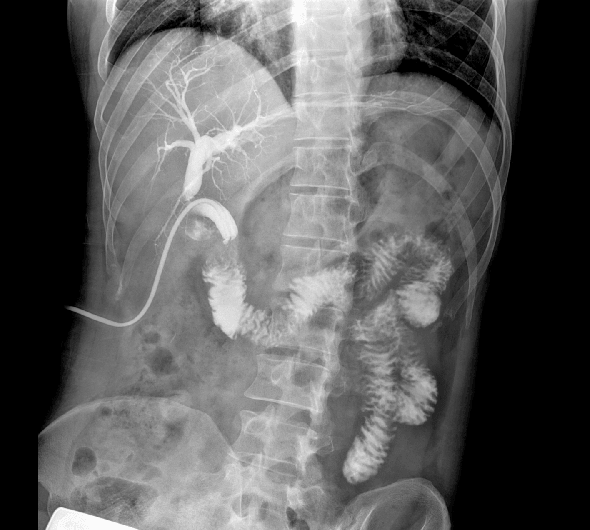

原厂优质影像链,搭载直接生长式碘化铯非晶硅平板,带来更加清晰锐利的图像效果。